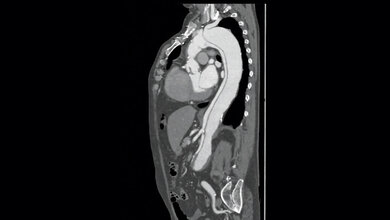

Inzwischen ist das Setzen eines Stents zur Routine geworden. Allein hierzulande werden etwa eine halbe Million Stents pro Jahr implantiert. Das Ziel ist die Behandlung von verengten Blutgefäßen, in der Regel eine Folge von Atherosklerose, um Schlaganfälle oder Herzinfarkte vorzubeugen oder die Folgen abzumildern. Fraunhofer gibt jedoch zu bedenken, dass die herkömmlichen Modelle aus Metall oder Polymeren beim Einsetzen das Endothel verletzen. Die Regeneration dieser Gewebeschicht dauere lange. Zudem bestehe ein erhöhtes Risiko für die Ausbildung von Thrombosen. Um Blutgerinnsel und damit Thrombosen im Stent zu verhindern, müssen Betroffene blutgerinnungshemmende Medikamente einnehmen.